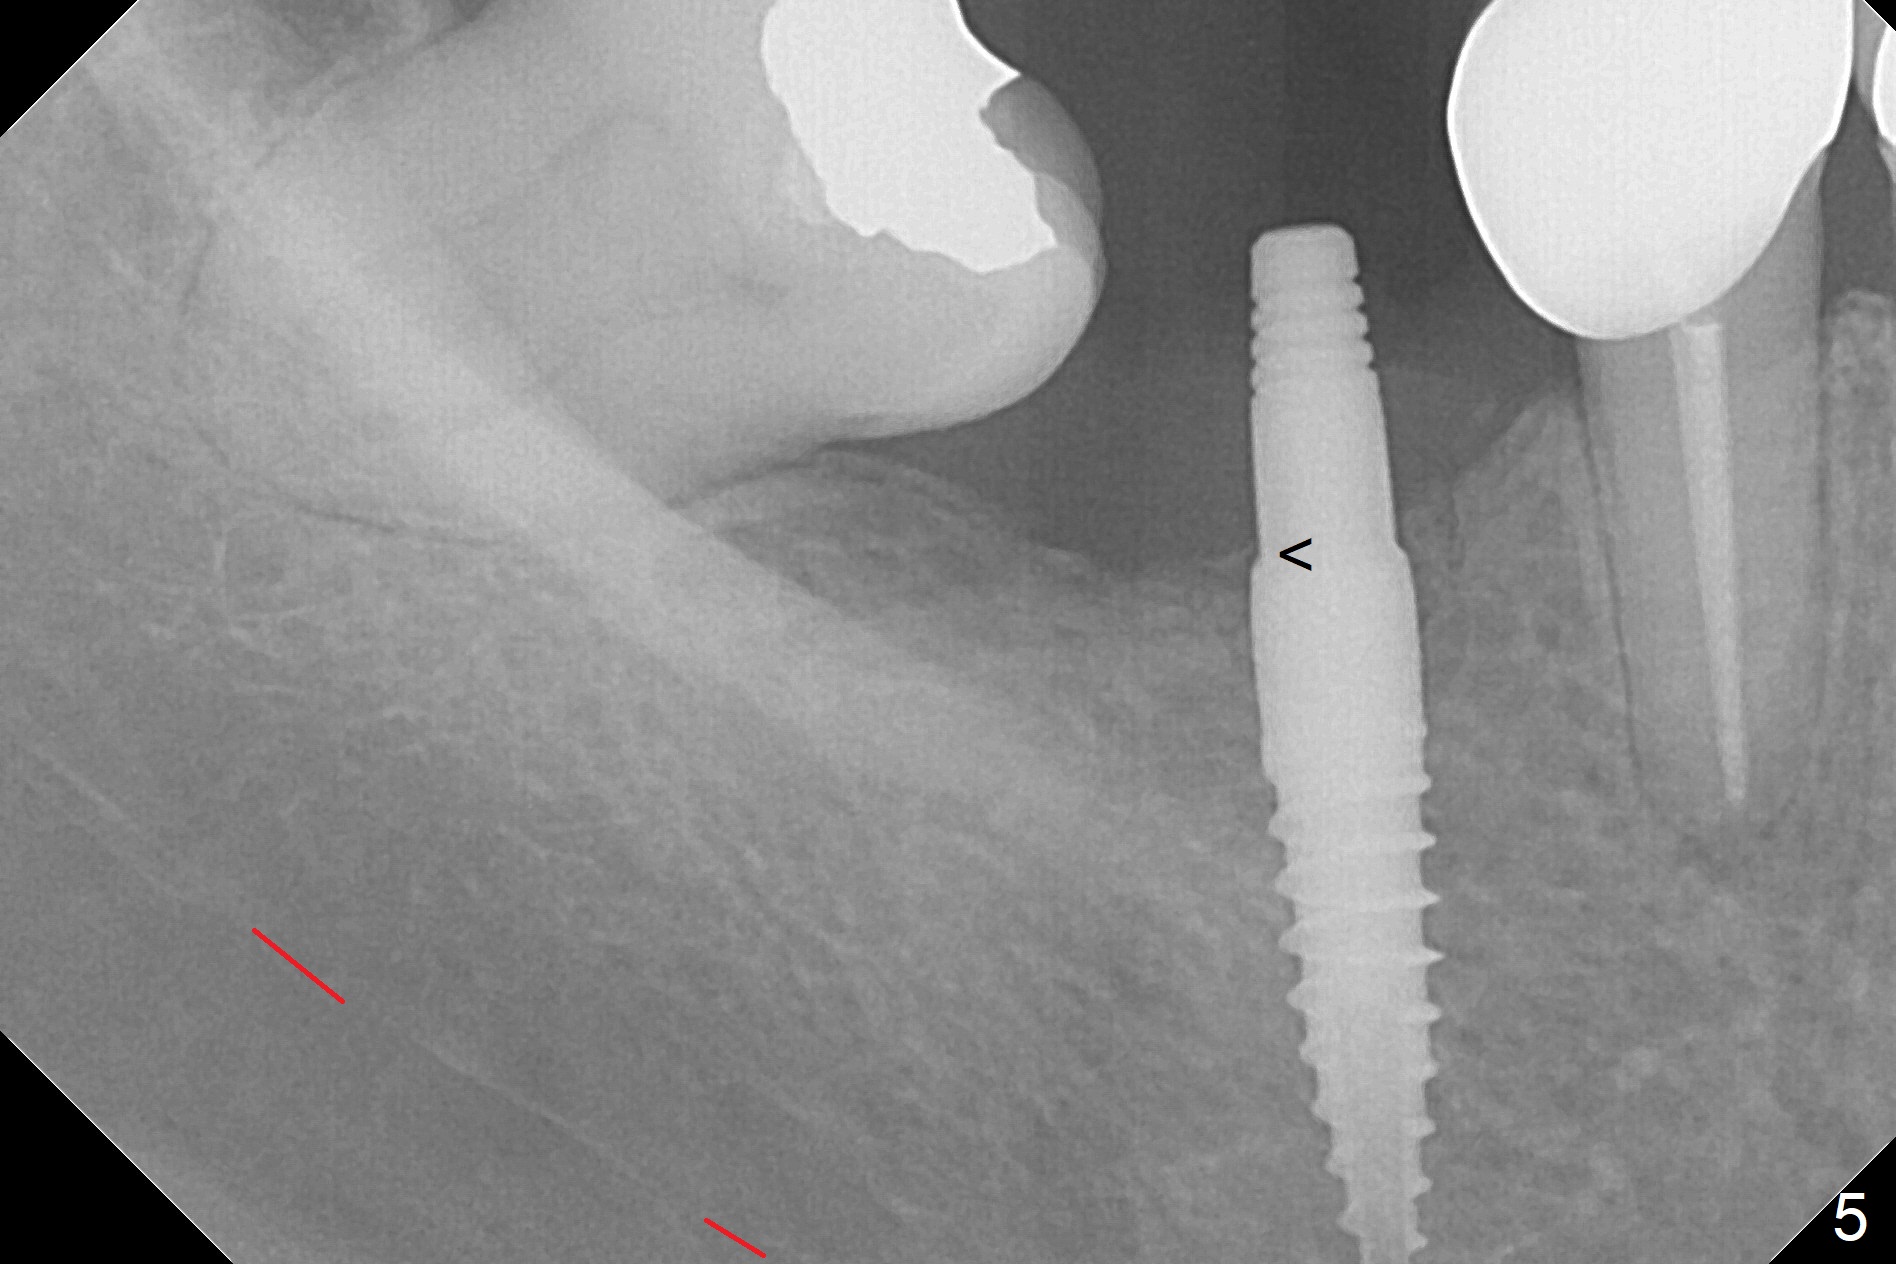

Incision reveals a narrow ridge and a narrow mesiodistal space at #30 (Fig.1).  It seems that a 1-piece implant is indicated.  Due to limited mouth opening, a 1.2 mm drill is unstable in place after use for 10 mm; instead a 1.5 mm drill is able to be inserted for 8 mm (Fig.2).  A 3x10(2) mm 1-piece dummy implant is placed with 40 Ncm at an apparently acceptable level (Fig.3 >).  Clinically a few threads are exposed buccally.  When a definitive implant with the same dimension is inserted with 45 Ncm, it looks seated too deep (Fig.4,5).  The latter is noted after suturing.  The implant is backed up for a few turns so that the length of the abutment appears a little more reasonable.  Introspectively, a 4 mm cuff should have been used after ridge reduction.  Although there is no bone loss 4 months postop (Fig.6), the abutment margin (Fig.7 arrow) is subgingival (red dashed line: gingival margin).  Diode laser is used for gingivectomy prior to impression.  The bone density around the implant increases 11 months post cementation (Fig.8 *), probably related to recurrent #18 infection.  The patient uses floss after meal.